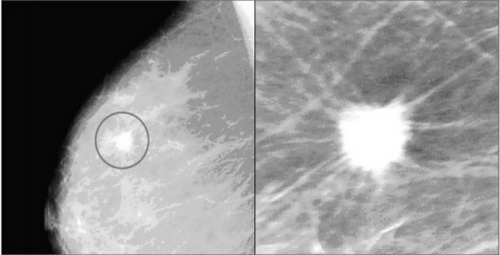

| Nốt vôi hóa trên vú qua hình ảnh chụp nhũ ảnh. |

Các nốt vôi hóa lớn (Macrocalcifications) xuất hiện với những đốm trắng và tròn lớn trên một tuyến vú và được phát tán một cách ngẫu nhiên trong các mô vú. Các nốt vôi hóa lớn khá phổ biến ở phụ nữ, đặc biệt là phụ nữ trên tuổi 50, đó là dấu hiệu tự nhiên của sự lão hóa vú. Các nốt vôi hóa lớn là lành tính (không phải ung thư) và không phải là mối quan tâm.

Vi vôi hóa hay các nốt vôi hóa nhỏ (microcalcifications) có kích thước rất nhỏ xuất hiện với nhiều đốm trắng nhỏ trên nhũ ảnh. Nói chung, vi vôi hóa vô hại. Tuy nhiên, nếu chúng xuất hiện thành chùm hoặc có giới hạn nhất định thì có thể là dấu hiệu của bệnh ung thư và cần phải được kiểm tra đầy đủ và chẩn đoán xác định.